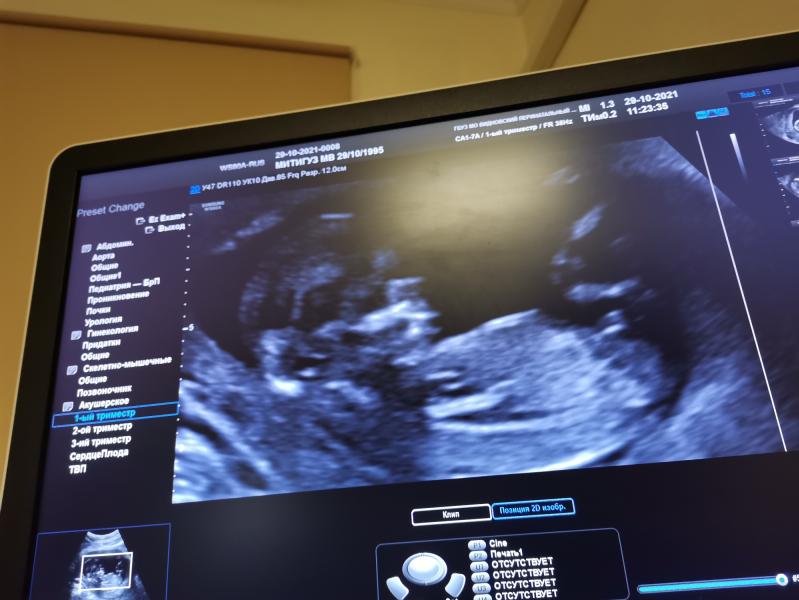

Кто думает?

Девочки, как думаете кто?

Девочки,как вы пытаетесь что-то там разглядеть))даже если опытные узисты не всегда это видят на таком сроке😃

Мне кажется мальчик, как то уж не ровно там))

Не видно бугорка тут🤷🏼‍♀️